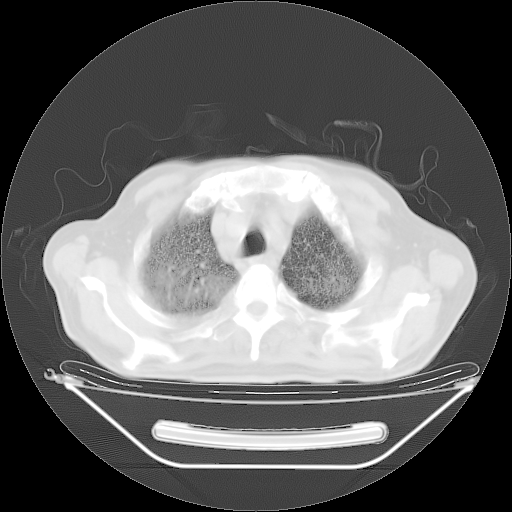

今天复查肺部CT,发现双肺广泛磨玻璃样改变。所以我把3月19日和5月9日相隔50天的肺部CT上传。请大家会诊。

2009年3月19日肺部CT片。

2009年3月19日肺部CT